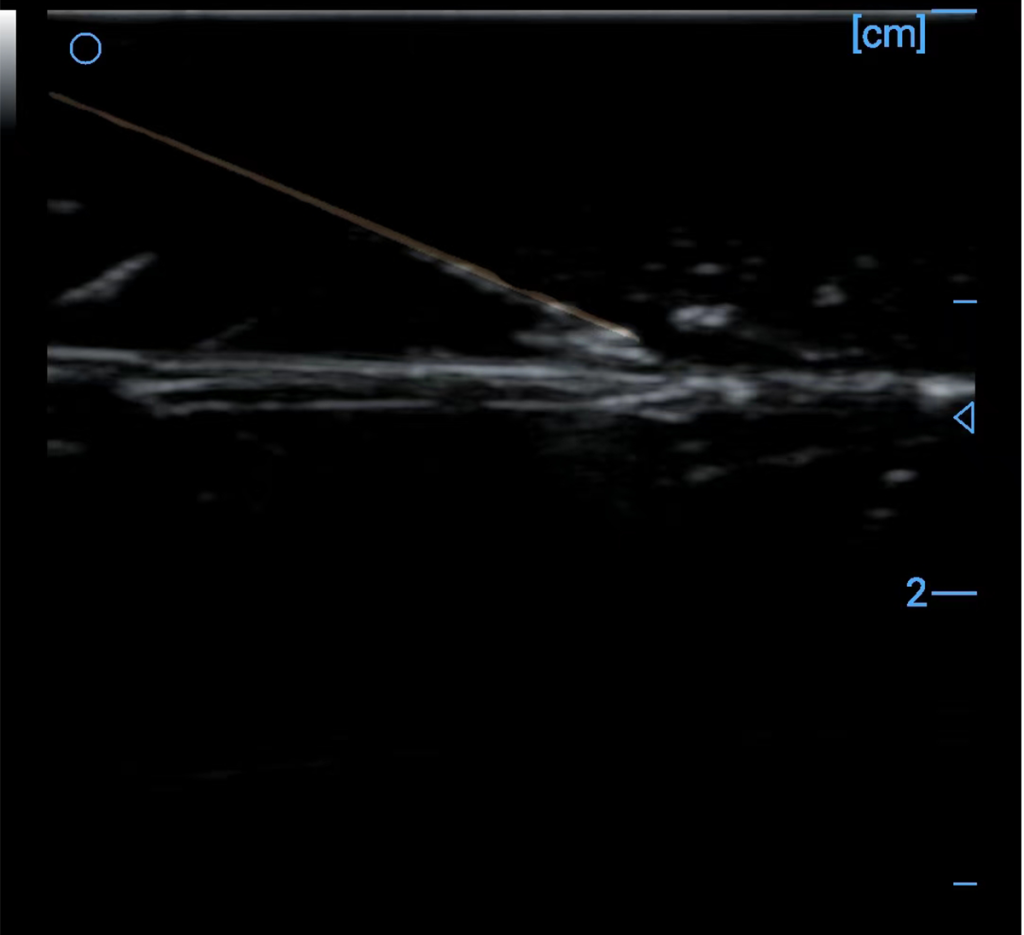

Spatial composite technology can effectively reduce speckle noise, thereby making uniform tissue images smoother and more delicate. It can also significantly improve the signal-to-noise ratio and contrast of the image, which is beneficial to clinicians’ diagnosis. In addition, scanning with different deflection angles can obtain information at different angles and detect interfaces in different directions, after spatial compounding, the image information is richer and the interface continuity is better. Another important application of spatial composite technology is puncture needle display enhancement. Through spatial composite deflection scanning, the incident sound beam is made as perpendicular to the surface of the puncture needle as possible, thereby obtaining a strong puncture needle surface image.

Needle enhancement